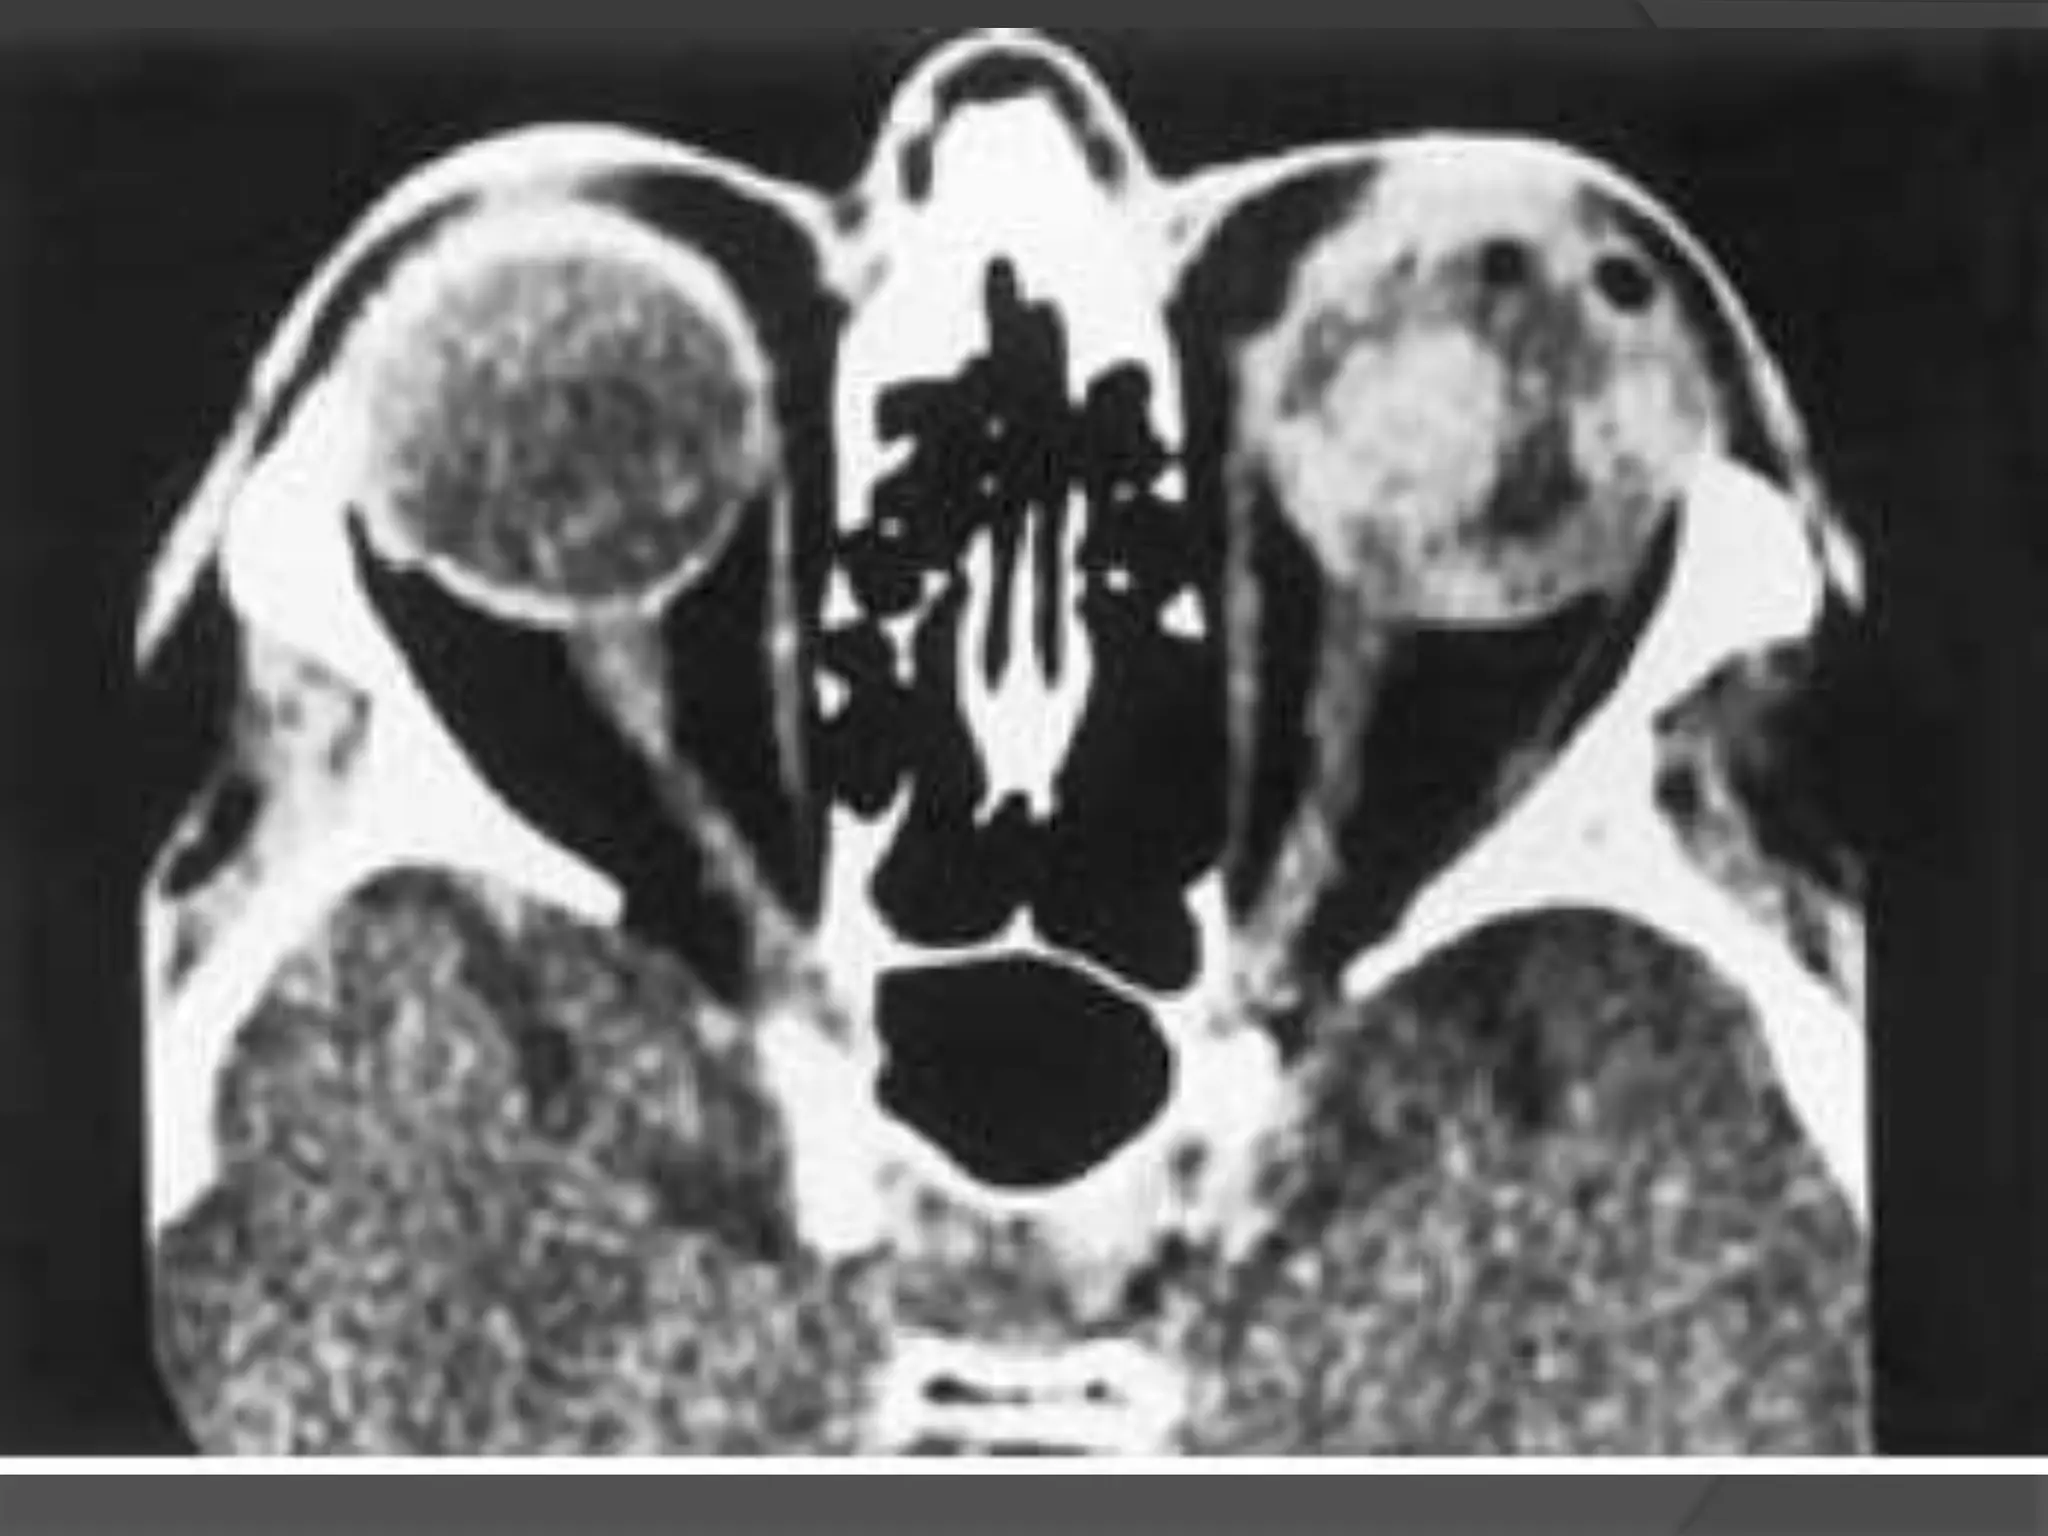

• #8 Colobomatous cyst. A, Axial CT scan shows bilateral microphthalmia and a large cyst (C) separated from the right globe by a band of enhancement (arrows), which is related to abnormal gliotic tissue. B, Anatomic section of an enucleated right eye. Note the small eye, large colobomatous defect, abnormal white tissues, gliotic tissues (G), and large cyst (C). Note the lens (L) and the optic nerve. C, Histologic section of an eye shows a large retinochoroidal coloboma (arrow), gliotic tissue (G ), cyst (C ), and lens (L).

• #9 Colobomatous cyst. Axial CT scan shows microphthalmic eyes with large cysts (arrows).